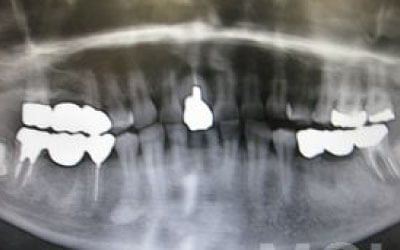

CTを使うと、骨や歯の状態を立体的に確認でき、正確な距離も測定できます。

骨の厚さや傾き、神経の位置などを事前に詳しく把握することで、安全にインプラント治療を行うことができるのです。

顎の骨の中には神経が通っており、インプラント治療の際にそれを傷つけてしまうリスクがあります。

しかし、当院では事前にCT撮影を行い、神経までの距離を三次元的に正確に把握した上で治療計画を立てるため、リスクをしっかり回避できます。

さらに、骨を削りすぎないようにするための専用のストッパーも導入しており、安全性には十分に配慮しています。